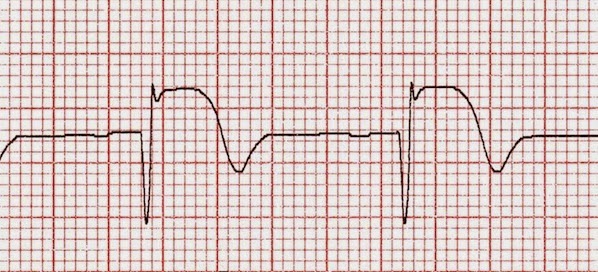

Estimular el barorreceptor carotídeo para bajar la presión arterial

05 septiembre 2017

Por primera vez se ensaya en humanos un tratamiento experimental para la hipertensión resistente, que utiliza un dispositivo intracarotídeo para activar el reflejo barorreceptor y producir descarga vagal e inhibición simpática. The Lancet, 1º de septiembre de 2017